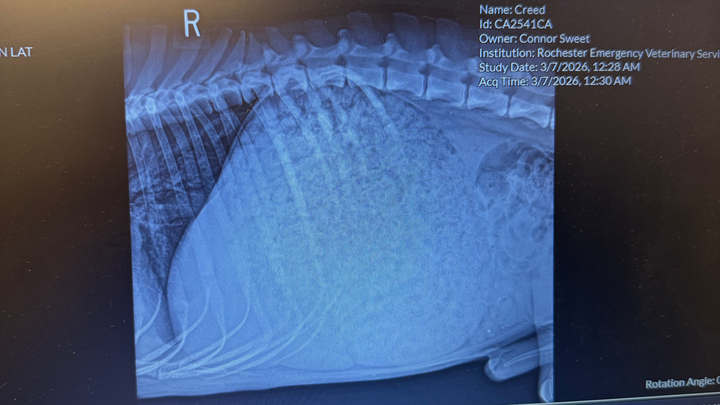

When we arrived around midnight, the emergency vet felt Creed’s lower stomach and immediately took him to the back room. He received a series of x-rays and an initial examination. To help him stay calm and comfortable, Creed had to be sedated and was given IV fluids. Creeds stomach was 3x the size of a normal stomach, for a deep chested GSD. His stomach was so large it was pushing his other organs together. He’s currently recovering overnight at the vet.